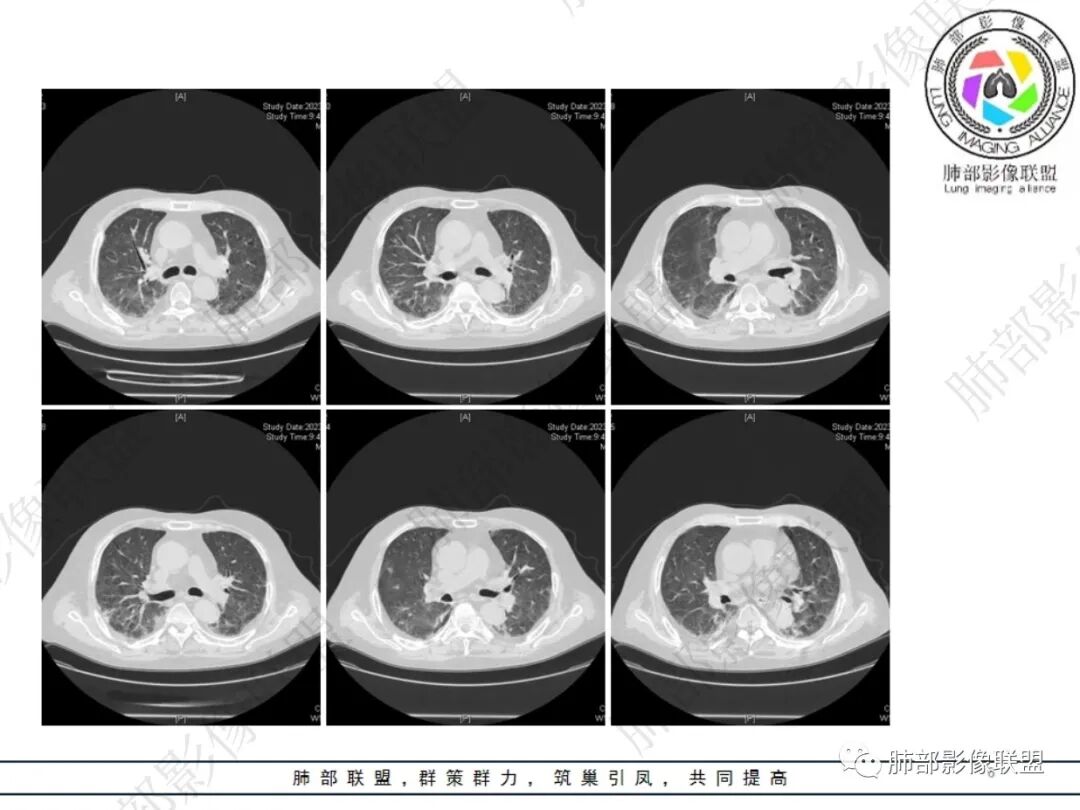

五、诊断:单从影像学上很难和其他疾病鉴别,以下信息可能提示奴卡菌感染可能:有慢性消耗性疾病长期使用激素、免疫抑制剂、肿瘤基础,不明原因发热、血象高,病程较长,应用广谱抗生素无效,影像学多种形态并存,边界相对清楚,易形成空洞,生化提示有低蛋白血症。培养找到奴卡菌有重要意义。

六、影像学表现:

①局限或弥漫肺部浸润影,可为GGO、斑片影、大部分以实变为主。

②单个或多个结节、团块影,结节大小不等,可见粟粒性结节。大部分为较大结节,易形成空洞。

③空洞:较为常见。

④累及胸膜,出现胸腔积液。